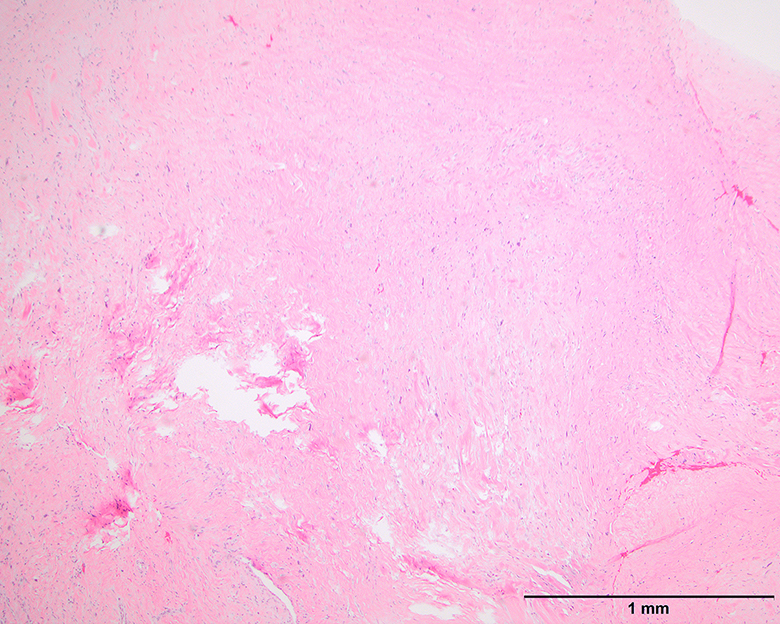

Microscopic (histologic) images

Contributed by Michael Clay, M.D., Melanie Bourgeau, M.D. and AFIP

Morphologic variability: